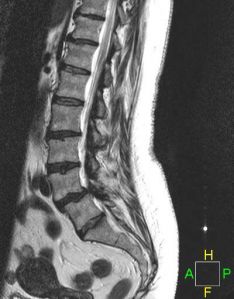

LUMBAR SPINAL STENOSIS